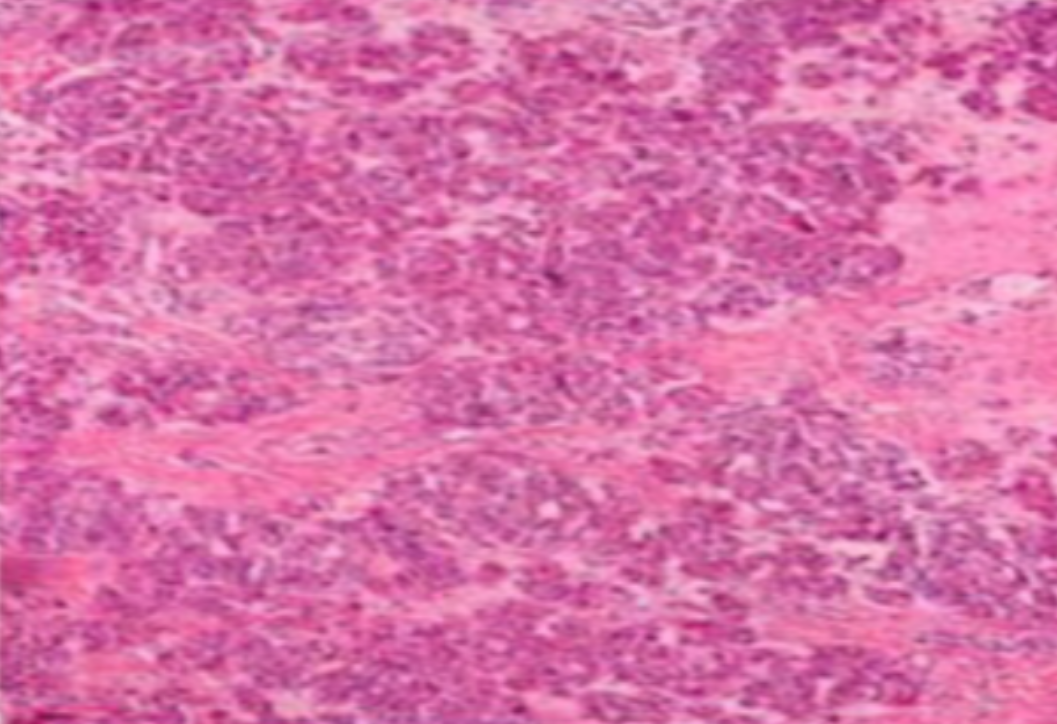

HE染色,全称苏木精-伊红染色法(Hematoxylin and Eosin staining),是最常见的组织切片染色技术之一,用于在显微镜下观察和分析组织或细胞的结构和形态。虽然HE染色是最常见且最基础的染色技术之一,😭但在实验过···

HE染色,全称苏木精-伊红染色法(Hematoxylin and Eosin staining),是最常见的组织切片染色技术之一,用于在显微镜下观察和分析组织或细胞的结构和形态。

虽然HE染色是最常见且最基础的染色技术之一,😭但在实验过程中,很容易出现各种情况导致染色切片质量参差不齐。所以,小编根据以往实验经验,给大家整理归纳出了15个HE染色中的常见问题,还包含问题原因分析以及解决方法哦~